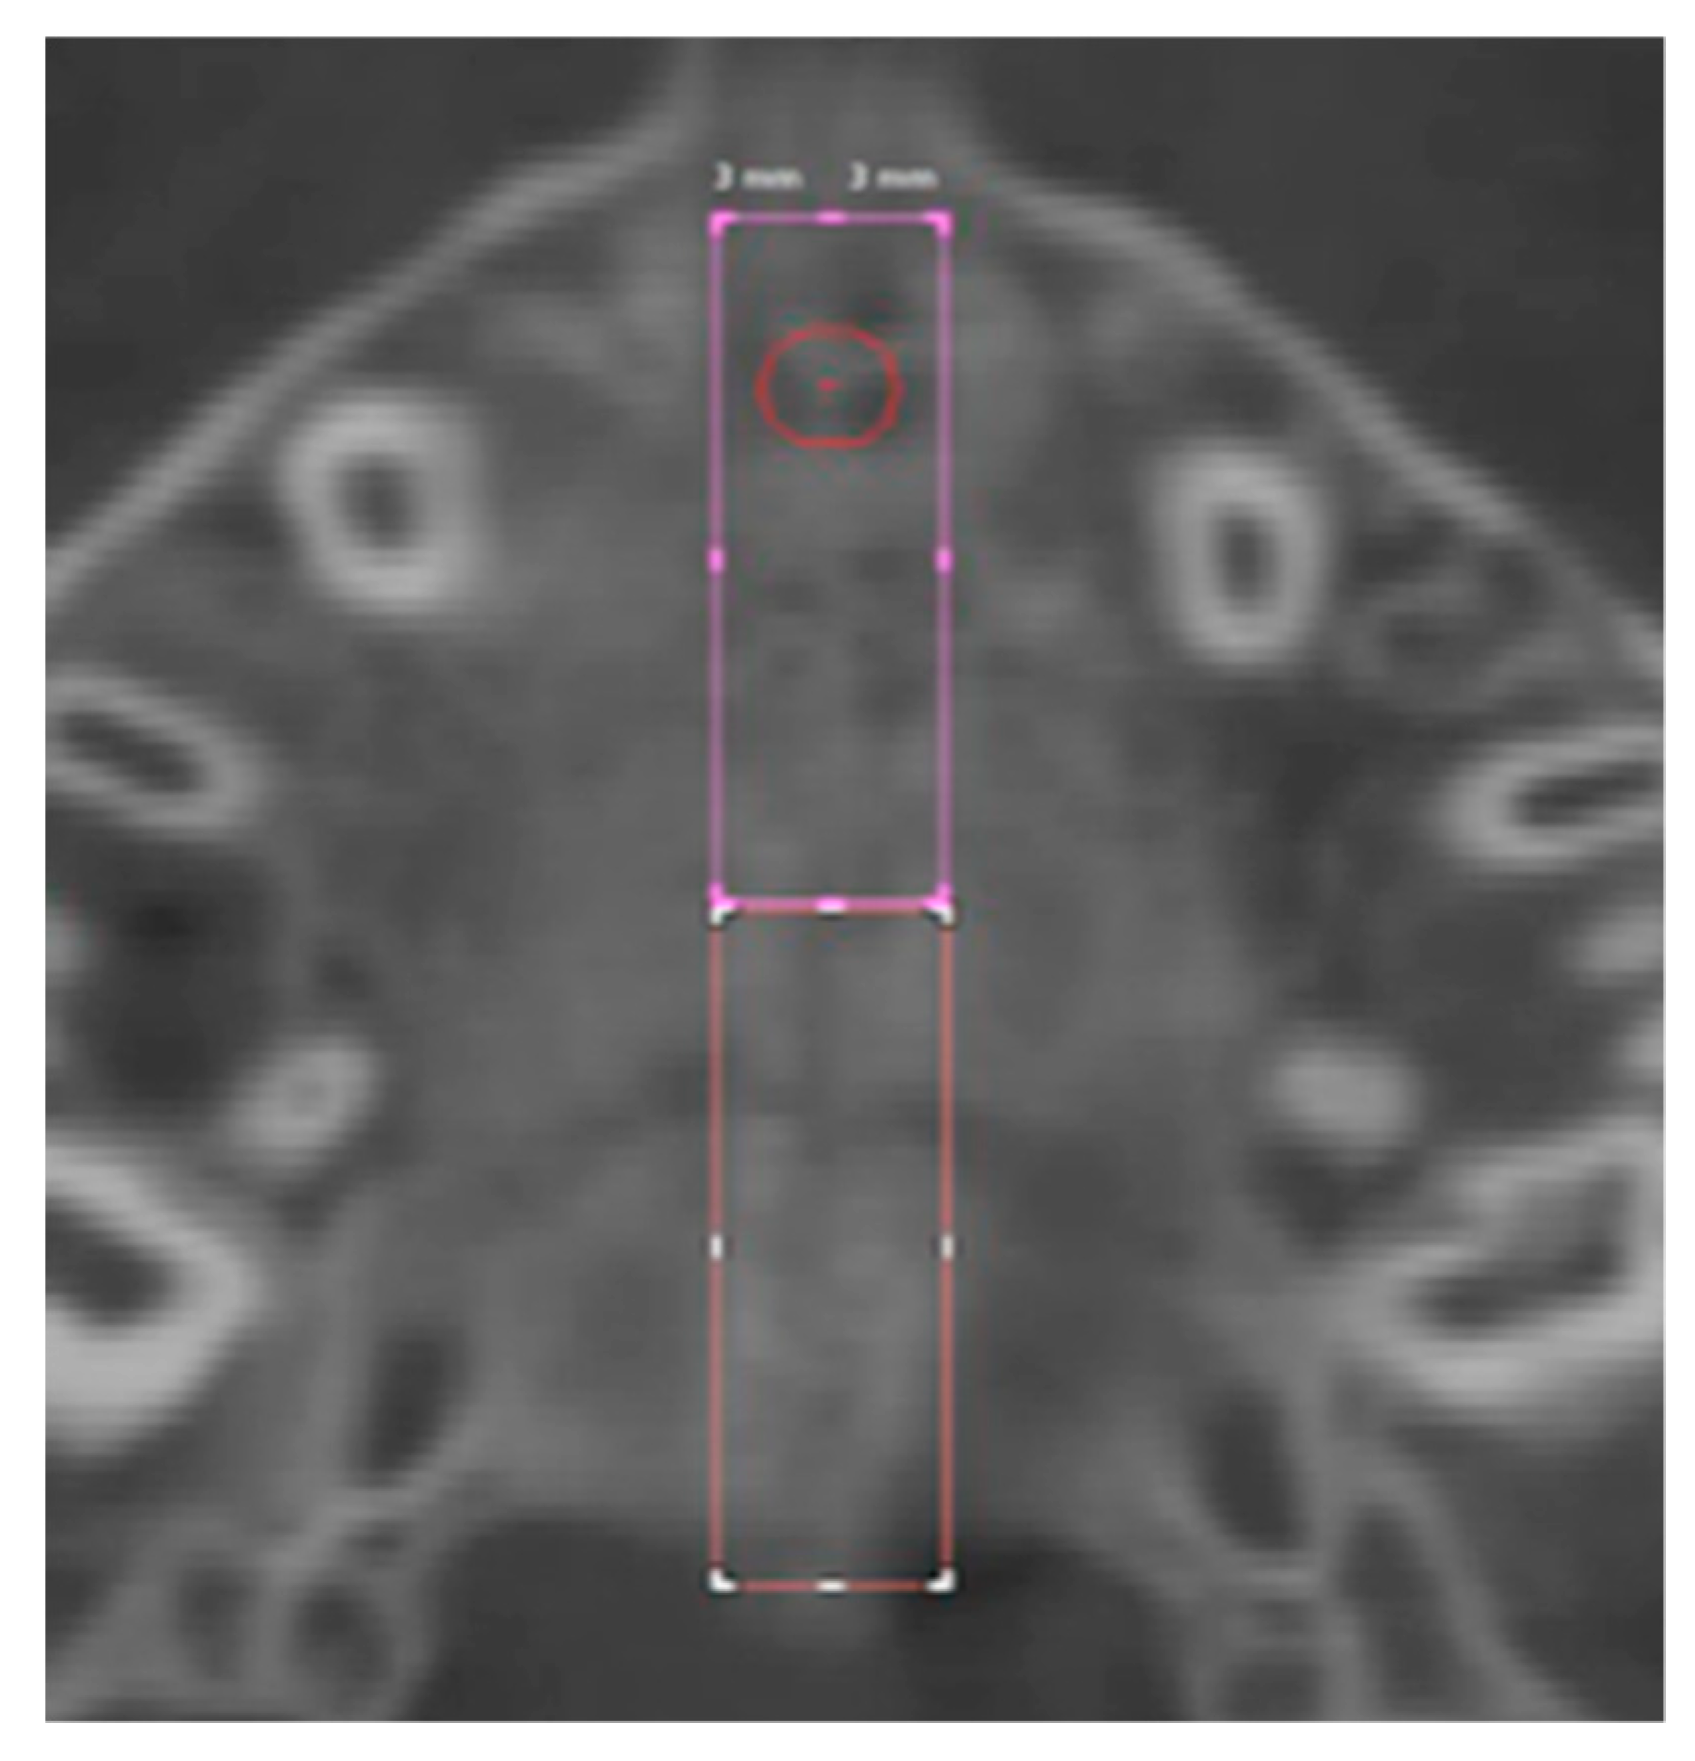

Six regions of interest (ROI) have been traced by one trained operator or the calculation of values of density in Hounsfield units (HU) using the software tools. Four round-shaped ROIs (Figure 3) and two rectangular-shaped ROIs (Figure 4) noted by previous studies [21,23] have been identified as follows.

2.1. Round-Shaped ROIs

Anterior suture (AS) ROI: values of density measured in the ROI located along the midpalatal suture 5 mm in front of the center of the nasopalatine duct.

Posterior suture (PS) ROI: values of density measured in the ROI located along the midpalatal suture 5 mm posterior to the center of the nasopalatine duct.

Anterior bone (AB) ROI: values of density measured in the ROI located in the maxillary bone 3 mm laterally to AS ROI (on the right side).

Posterior bone (PB) ROI: values of density measured in the ROI located in the maxillary bone 3 mm laterally to PS ROI (on the right side).

Figure 3. Round-shaped ROIs in the palatal region.